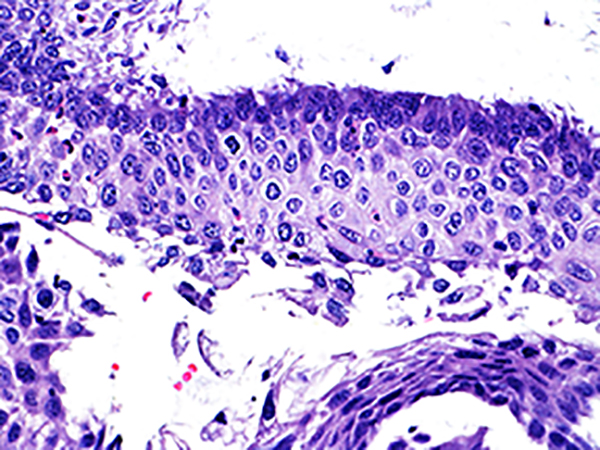

![]() Case 1

Area 2 - Soft Bx CIN 2 40x - High Power |